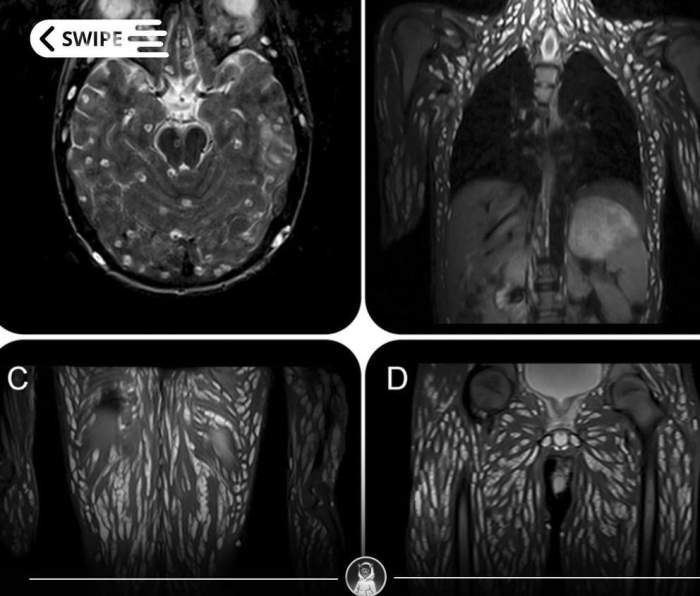

O femeie care a consumat carne de porc crudă în mod regulat timp de zece ani a ajuns la spital cu o infecție parazitară gravă, iar radiografiile realizate de medici au dezvăluit o imagine șocantă.

În urma investigațiilor, s-a descoperit existența a zeci de formațiuni calcificate, răspândite în tot corpul, de la mușchi și țesuturi moi până în apropierea articulațiilor.

Medicii au explicat că larvele parazitare au pătruns inițial în intestine, după care s-au răspândit treptat în organism, unde s-au transformat în capsule dense, greu de detectat în fazele timpurii.

Aceste formațiuni pot rămâne ani întregi în corp fără să provoace simptome evidente, dar în timp distrug țesutul înconjurător.

Pe radiografii și scanări CT, infecția apare sub forma unor „puncte” calcificate, asemănătoare unor corpuri străine dispersate. În realitate, aceste puncte sunt capsule parazitare întărite, rămășițe ale larvelor care au migrat prin corp înainte de a se stabiliza.

Medicii spun că, odată cu evoluția infecției, pacienții încep să se confrunte cu: dureri musculare persistente, umflături, o stare de slăbiciune generală, dureri de cap și oboseală cronică.

Netratată ani la rând, o astfel de infecție poate produce leziuni greu sau chiar imposibil de reparat.